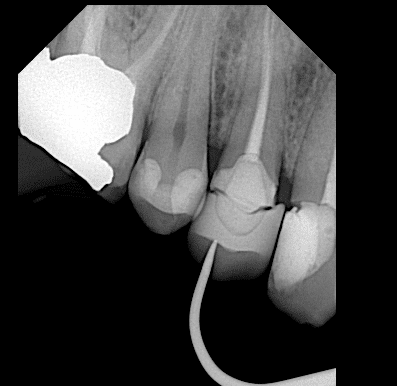

X ray after biobase

Firstly during trying the restoration I take x ray and see the overhang so I returned it to the lab to correct the overhang

Now the fitness is good